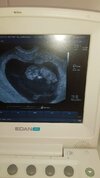

Dziewczyny jestem po wizycie, wszystko jest dobrze. Lekarz mówi że wszystko ok, wspomniał że można umawiać się na wizytę badań prenatalnych. Wyszłam zadowolona, a w domu patrzyłam na zdjęcie dzidzi i wpadłam w jakaś panikę. Popatrzyłam na zdjęcie USG i poczytałam o przezierności karkowej i patrzę na to moje USG i chociaż jest jeszcze kilka dni do ukończenia 11 tygodnia to mi wydaje się przezorność taka duża. Zobaczcie proszę. Wiem że to nie mozna gołym okiem ocenić, ale odstęp jest taki spory wydaje mi się. Wpadam dziewczyny w jakaś chorą panikę.

Ja lekarzem nie jestem ale nie wydaje mi się żebym wiedziała tam coś niepokojącego. A miałam córkę z przyziernością powiększoną i uwierz mi że wtedy to to bardzo widać... śliczny mały ludzik ♡

Ja tez się nie znam. Ale skoro lekarz powiedział że okej to okej. Nie doszukuj się. Ja bym nawet nie wpadła żeby tak oglądać zdjęcie. Głęboki oddech i czekamy do prenatalnych 😊😚 Ja na początku analizowałam wszystko, kształt pęcherzyka, cialko zolte, te wszystkie napisy na zdjęciu.. to nie ma sensu, skoro lekarz nie powiedział ze widzi cos niepokojącego

naprawdę nie doszukuj się… lekarz na pewno by zwrócił uwagę gdyby coś miało być nie tak. Czekak spokojnie na prenatalne. Zdjęcie piękne! 😍